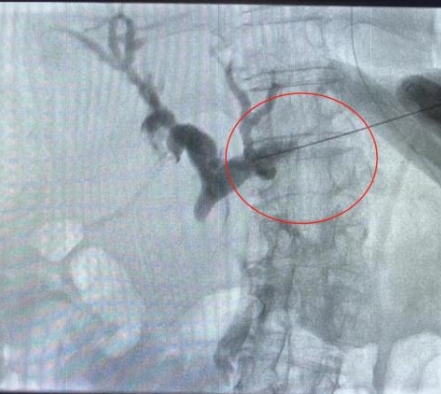

由于患者肝右葉占位巨大,完全遮擋右側(cè)穿刺路徑,左肝管為唯一穿刺路徑。介入科彭鵬醫(yī)生與重癥醫(yī)學(xué)科討論后,征得患者家屬同意后,擬行左側(cè)經(jīng)皮肝內(nèi)膽管穿刺引流術(shù)。術(shù)中一針便成功進入膽道系統(tǒng),導(dǎo)絲引流管放置順利,造影顯示膽道系統(tǒng)顯影滿意,側(cè)孔位置可,引流順暢,37分鐘便結(jié)束了手術(shù),術(shù)后順利轉(zhuǎn)入普外科護理治療。這例手術(shù)的成功開展,刷新了該院介入團隊高齡患者手術(shù)的新記錄!

經(jīng)皮肝內(nèi)膽管穿刺引流術(shù)是在醫(yī)學(xué)影像的引導(dǎo)下,利用穿刺針經(jīng)皮穿入肝內(nèi)膽管,注入對比劑,使肝內(nèi)外膽管迅速顯影后,置管引流以緩解梗阻癥狀。對于惡性梗阻性黃疸患者,通過該方式可降低血清膽紅素,有助于恢復(fù)肝腎功能,提高其生存質(zhì)量,延長生存期,部分患者還可獲得進一步治療的機會。對于良性梗阻性黃疸患者,除有利于迅速緩解黃疸和感染等癥狀外,還可為后續(xù)治療提供通道。